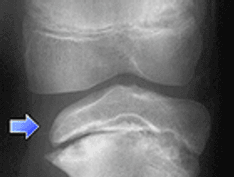

Radiograph of a patient who is skeletally mature. Note that the tibial tubercle is enlarged and there is an ossicle. A bursa was overlying this.

Radiograph of a patient who is skeletally immature. The tubercle is elongated and fragmented.

Courtesy of John T Killion, MD, OSA Pediatric Orthopaedics.